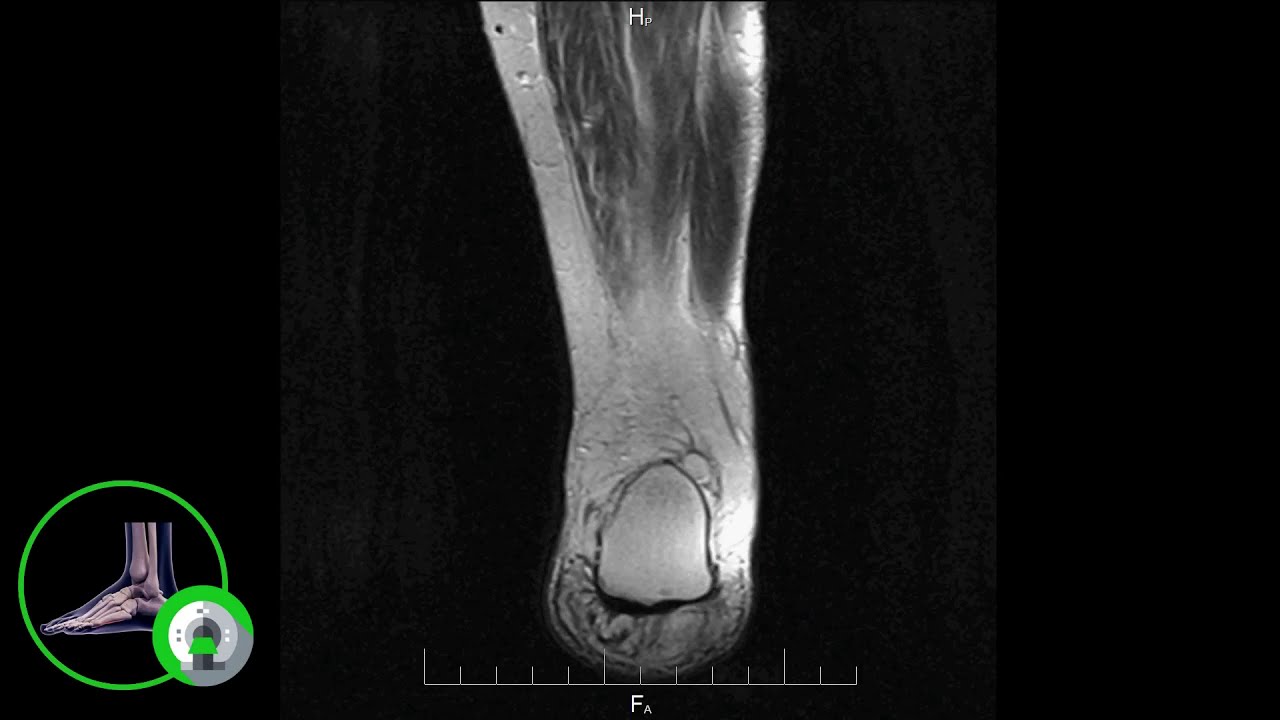

Что покажут снимки МРТ голеностопного сустава при разрыве связок

- Хорошая оценка мягких тканей

- Полный разрыв визуализируется как прерывистость и волнистость связки

- Частичный разрыв вызывает утолщение и повышение интенсивности сигнала связки

- Возможно костнохрящевое поражение в таранной кости и (особенно при тяжелой травме) повреждение с противоположной стороны сустава в дистальном отделе большеберцовой кости (гиперинтенсивное на Т2-взвешенном изобра¬жении и гипоинтенсивное на Т1-взвешенном изображении; возможен костно-хрящевой перелом)

- Расширение суставной щели и расхожде¬ние синдесмоза — признаки разрыва

- Обычно наблюдается выпот в по¬лости сустава и припухлость мягких тканей

- Прямая МР-артрография четко определяет костно-хрящевые поражения (хрящевой покров, ста¬бильность) и свободные и костно-хрящевые хлопья

- Поздние осложнения: синдром предплюсневого канала, переднее (костный) или переднебоковое (мягких тканей) столкновение костей голеностопного сустава (импинджмент-синдром).

а,b Разрыв латеральной связки голеностопного сустава. Парааксиальная МРТ: (а) проксимальная, (b) дистальная. Разрыв передней таранно-малоберцовой (а, стрелка) и пяточно-малоберцовой связок (b), каждая демонстрирует прерывистость, волнистость и расхождение краев. Выпот в полости сустава и припухлость мягких тканей. Повреждение удерживателя мышц (b).